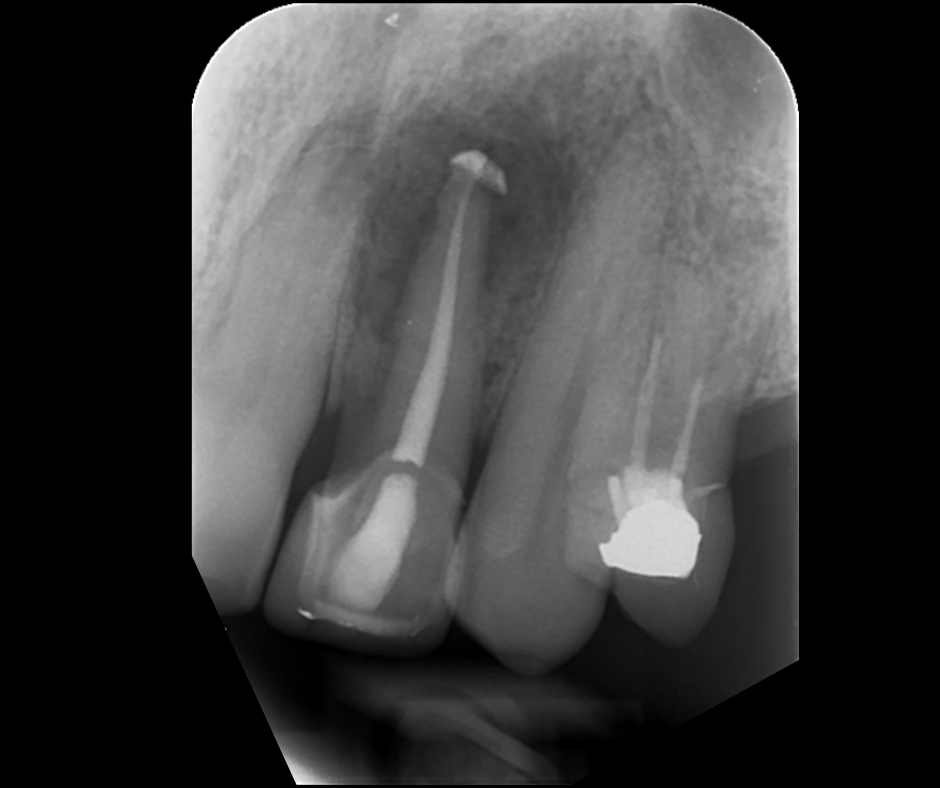

This course focuses on modern single-file endodontic systems, guiding participants through diagnosis, case assessment, access cavity design, canal location, root canal system preparation, and obturation techniques.

• To re-examine access cavity design and its importance in endodontic success

• To understand the importance of achieving patency and mechanical glidepath with hand & NiTi instruments

16.20 – 18.00 – Obturation and Orifice seal